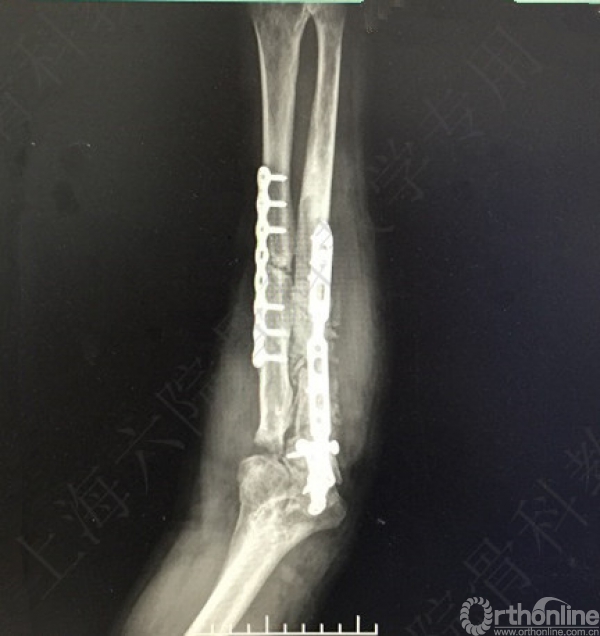

术后X线片示:左尺桡骨骨不连术后,对位对线可,内固定牢靠,桡骨头切除,肘关节在位。

医方第一次术后,未能纠正骨折力线,未发现桡骨头脱位,手术方式和操作欠妥当。存在对疾病评估不足,漏诊,手术方式不当,手术操作不当,术后并发症观察及处理不当等过失。